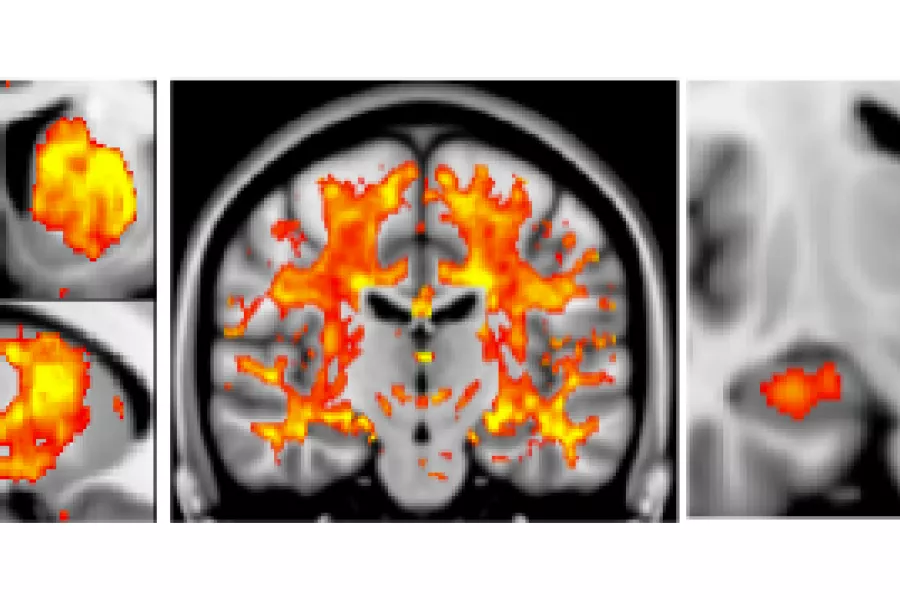

The Oxford Brain Imaging Genetics (BIG) Browser is part of a collaboration between the research groups of Prof Jonathan Marchini and Prof Steve Smith at fMRIB in Oxford. This collaboration aims to uncover the genetic basis of human brain imaging measures using the UK Biobank project. It is expected that this research will help uncover the genetic influences of neurodegenerative and psychiatric diseases such as Alzheimer’s, Parkinson’s, Schizophrenia and Depression. The UK Biobank is following the health and well-being of 500,000 volunteer participants. So far the project has collected genetic data on all 500,000 participants and is in the process of collecting brain imaging data on 100,000 participants, with brain imaging data on ~10,000 participants. Both Prof Marchini’s and Prof Smith's groups have been centrally involved in the processing and analysis of genetic data and imaging data respectively. Combining the genetic and imaging data is complex and is made much easier by pooling expertise across the two groups. In the course of their research they have uncovered several hundred loci (positions) in the human genome associated with structural and functional measures of the human brain. They have posted a paper on bioRxiv on the imaging genetic work and a paper on the analysis of the genetic data. The Oxford BIG Browser hosts the results from the imaging genetics paper and allows researchers to quickly and clearly visualize and explore the results. They have made this data available ahead of publication to best facilitate the research of other groups in this area.